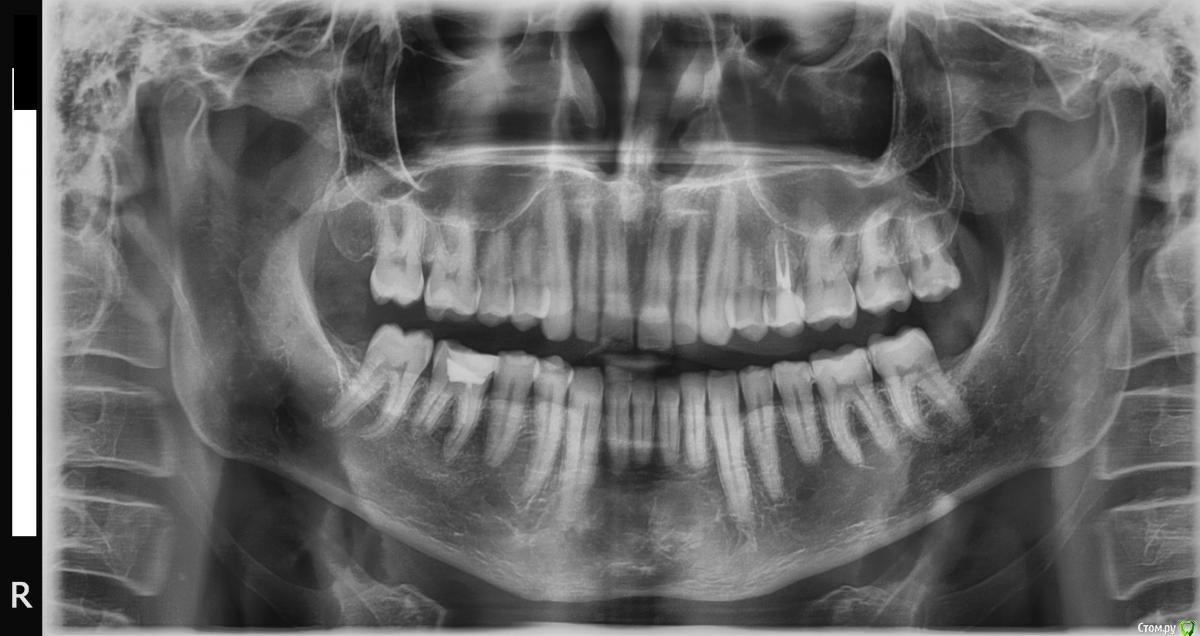

Дмитрий555 Опубликовано 4 февраля, 2016 Автор Поделиться Опубликовано 4 февраля, 2016 панораму сделал. Посмотрите пожалуйста Ссылка на комментарий

IvanK Опубликовано 4 февраля, 2016 Поделиться Опубликовано 4 февраля, 2016 в итоге ничего страшного это часть кости, ее нужно сошлифовать и все 27 и 46 нуждаются в лечении 28 кандидат на удаление Ссылка на комментарий

Дмитрий555 Опубликовано 5 февраля, 2016 Автор Поделиться Опубликовано 5 февраля, 2016 спасибо, буду лечить все перечисленные. Сегодня был в клинике, сделали 1 зуб передний, в квитанции не указано какой, и сделали полировку передних от зубного камня. По поводу этой болячки, о которой я начал тему, сказали, что возможно это что-то там отросло или проросло на месте удалённого зуба. Простите, дословно не могу воспроизвести, стресс и всё такое. Но если будет надо, то при следующем посещении можно будет этот кусочек зацепить и выдернуть. Но пока на нём не жую, беспокоить перестал. Панорамный снимок до сих пор рассматриваю, завораживает. Поставил картинкой на рабочий стол Ссылка на комментарий